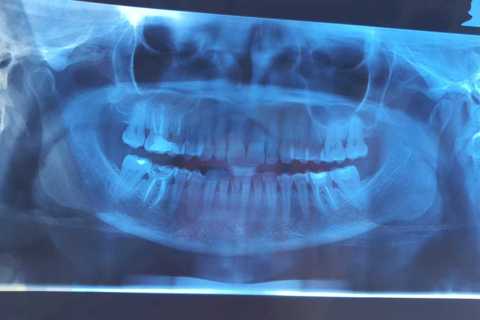

Paciente compareceu ao consultório com fratura de restauraç˜so em resina no elemento 36 e foi realizado bloco em ceramica pura e-max cor 3M2